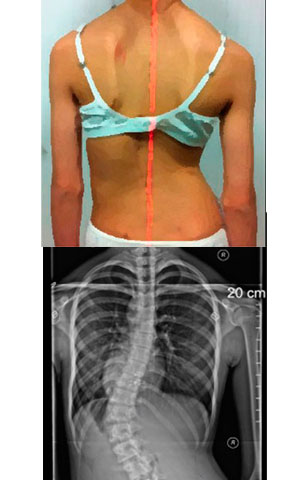

Despistaje de Escoliosis: que buscar

¿Qué es lo que buscan?

Hay ciertas cosas que pueden detectarse:

- Un hombro más alto que otro

- Un omoplato (escápula) más prominente que el otro

- Una cadera más alta que la otra

- Una pierna parece más larga

- El tronco y la parrilla costal están desplazados hacia un lado

- La cabeza no está centrada sobre la pelvis

- Asimetría de la cintura

- La ropa cuelga de manera asimétrica y cuando el/la niño/ niña se inclinan hacia delante por la cintura, un lado parece más alto

Algunos de estos signos de escoliosis pueden ser difíciles de detectar, especialmente para el observador no entrenado. |

TEST DE ADAMS

- El examinador solicita al paciente que se incline hacia adelante con los brazos flojos y las rodilla extendidas.

- Se observan los hemitórax (que deben ser simétricos).

- Si existe una asimetría a nivel torácico o lumbar, se dice que la maniobra de Adams es positiva y se debe descartar una escoliosis solicitándole radiografía

La Escoliosis produce la formación de una giba torácica (prominencia de los arcos costales en un lado del tórax) y una giba lumbar (por el deslizamiento de los músculos que están encima de estas vertebras). |

Hemos apreciado signos de escoliosis. ¿Cuál es el siguiente paso?

- Debe ser evaluado por un especialista para una exploración detallada.

- Será preciso realizar una radiografía para confirmar el diagnóstico de escoliosis.

- Las radiografías deben realizarse con el paciente de pie y erguido. Para valorar mejor la alineación global de la columna vertebral, deben incluirse todas las regiones de la columna en una misma placa, en lugar de obtener radiografías individuales de cada región.

La radiografía que debe realizarse se denomina: Espinograma o Columna Panorámica |

Diagnostico

La Escoliosis produce la formación de una giba torácica (prominencia de los arcos costales en un lado del tórax) y una giba lumbar (por el deslizamiento de los músculos que están encima de estas vertebras).